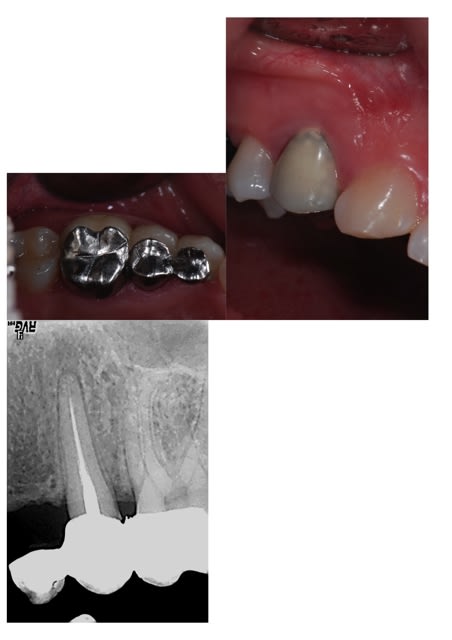

Bizarre la cuspide palatine de la 5 ne correspond pas au bridge cantilever CIV ni à la radio... y aurait-il deux secteurs différents ??

le cantilever est à gauche et la civ est à droite, bien vu! dans mon bilan, je n'ai pas évoqué l'endo de la 25 mais il y a aussi du boulot ;-)

bon, j'ai quand même été scotché par la sculpture occlusale à la fraise boule, comme au temps des Bagues Ajustées, et par les espaces interdentaires totalement bouchés; pour l'endo à reprendre, ça se trouve encore par chez nous